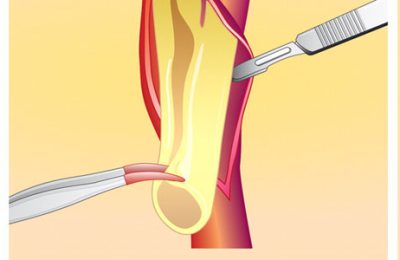

Anevrizmanın klasik cerrahi tedavisi ameliyat ile genişlemiş damar bölümünün suni bir damar ile değiştirilmesidir. Bu yöntem yaklaşık 50 yıldır kullanılmakta olup, güvenilir ve kalıcı sonuçlar sağlamaktadır. Ameliyat genel anestezi altında karından büyük bir kesi yapılarak gerçekleştirilir ve bir sorun olmadığı takdirde hastalar ameliyat sonrası 7-10 gün içinde taburcu edilirler. Hastaların normal yaşamlarına dönmeleri 1-2 ay sürebilir. Bu yöntem anevrizmayı tamamen tedavi edebilen bir yöntemdir. Ancak büyük bir ameliyat olmasından dolayı ameliyata bağlı ölüm riski ortalama %5 dir.

Daha az rahatsızlık verebilecek bir başka tedavi yöntemi ise özel bazı kateterler ile damarın içine girilip, anevrizmanın olduğu damar bölümüne içerden suni damarın yerleştirilmesidir. Endovasküler (damar içinden) anevrizma onarımı olarak bilinen bu yöntem yaklaşık 10 yıllık bir geçmişe sahiptir. Bu yöntemde karından kesi yapılmayıp, sadece kasıklardan yapılan küçük kesiler aracılığı ile röntgen altında işlem gerçekleştirilir.

Anevrizmanın olduğu yere getirilen suni damar şişirilir ev dikiş yerine içerden özel kancalar ile damar tutturulur. Hastalar işlem sonrası hastanede bir iki gün yatıp taburcu edilirler. Bu yöntem anevrizmalı hastaların ancak bir bölümü için uygundur. Anevrizmanın içine suni damar yerleştirildikten sonra anevrizma büyümeye devam edebilir hatta rüptüre olabilir. Bu yüzden hastaların işlem sonrası aralıklı olarak bilgisayarlı tomografi veya renkli Doppler ultrasonografi ile takibi gereklidir. Bu açıdan bu yöntem açık ameliyat yönteminin tersine anevrizmayı her zaman kalıcı olarak tedavi etmez.